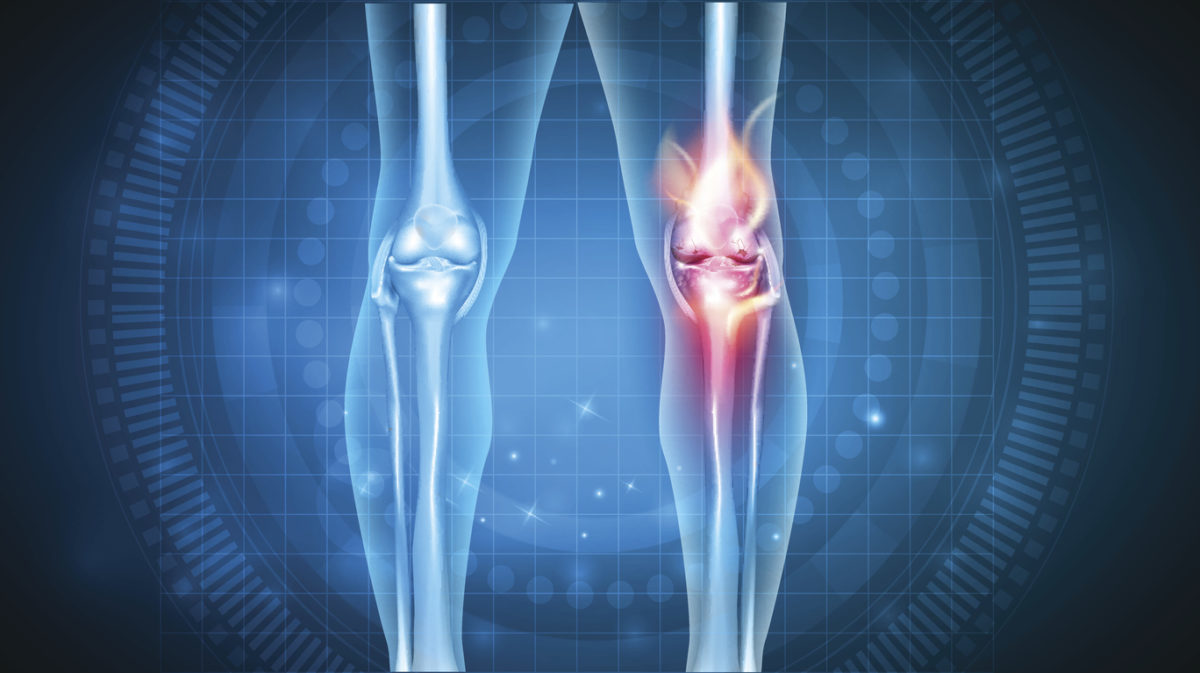

Η ρευματοειδής αρθρίτιδα προσβάλλει τις αρθρώσεις και στις δύο πλευρές του σώματος, δηλαδή και στα δύο χέρια, και στους δύο καρπούς, ή και στα δύο γόνατα. Αυτή η συμμετρία είναι που την ξεχωρίζει από τους άλλους τύπους αρθρίτιδας.

Σε άτομα με ΡΑ, το ανοσοποιητικό σύστημα προσβάλλει εσφαλμένα τα κύτταρα στην εσωτερική επένδυση των αρθρώσεων, με αποτέλεσμα την φλεγμονή τους. Αυτό κάνει τις αρθρώσεις να πρηστούν, να σκληρύνουν και να σας πονούν.